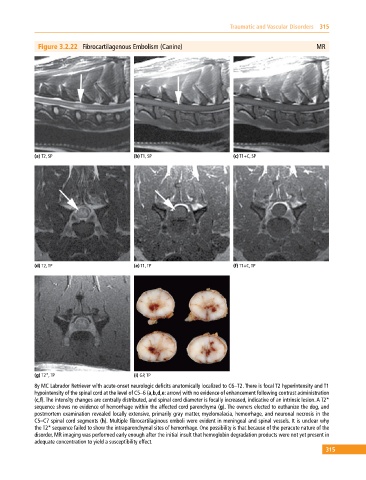

Figure 3.2.22 Fibrocartilagenous Embolism (Canine) MR

(a) T2, SP (b) T1, SP (c) T1+C, SP

(d) T2, TP (e) T1, TP (f) T1+C, TP

(g) T2*, TP (i) GP, TP

8y MC Labrador Retriever with acute‐onset neurologic deficits anatomically localized to C6–T2. There is focal T2 hyperintensity and T1

hypointensity of the spinal cord at the level of C5–6 (a,b,d,e: arrow) with no evidence of enhancement following contrast administration

(c,f). The intensity changes are centrally distributed, and spinal cord diameter is focally increased, indicative of an intrinsic lesion. A T2*

sequence shows no evidence of hemorrhage within the affected cord parenchyma (g). The owners elected to euthanize the dog, and

postmortem examination revealed locally extensive, primarily gray matter, myelomalacia, hemorrhage, and neuronal necrosis in the

C5–C7 spinal cord segments (h). Multiple fibrocartilaginous emboli were evident in meningeal and spinal vessels. It is unclear why

the T2* sequence failed to show the intraparenchymal sites of hemorrhage. One possibility is that because of the peracute nature of the

disorder, MR imaging was performed early enough after the initial insult that hemoglobin degradation products were not yet present in

adequate concentration to yield a susceptibility effect.